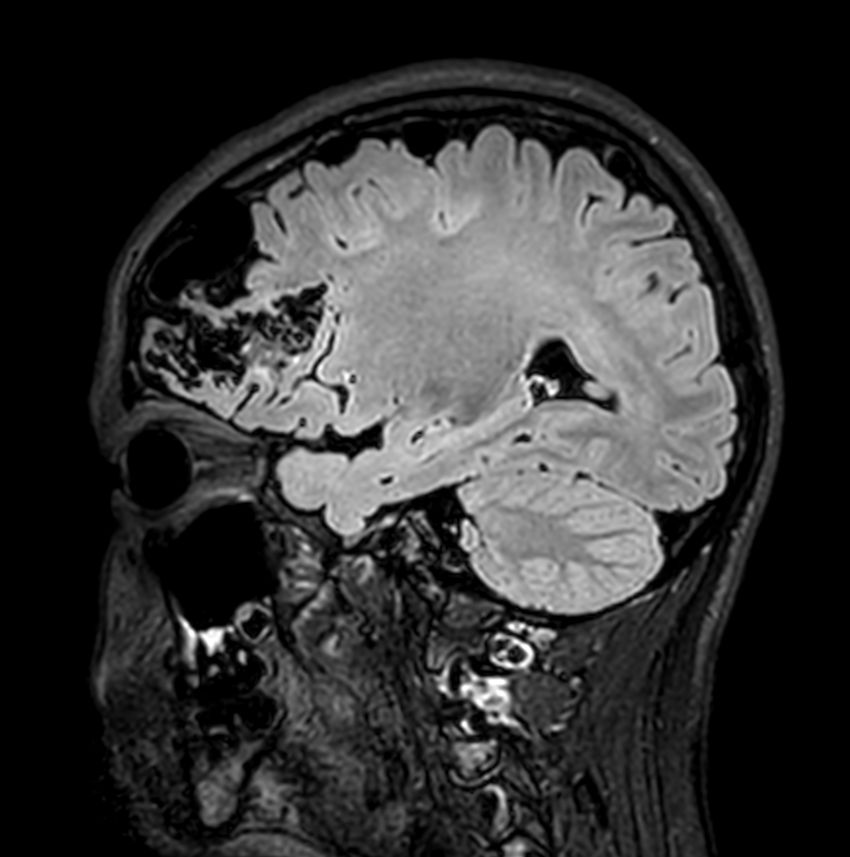

Pediatric brain with AVM

Pediatric patient with frontal brain AVM. MultiVane XD is used to achieve high resolution diagnostic images, even in the case of severe patient motion. SWIp sequence is added to acquire exquisite susceptibility contrast. The 3D sequences with isotropic voxel size enable reformats in any plane without loss of resolution. And 4D-TRAK XD, a fast, dynamic contrast-enhanced MR Angiography method allows to achieve high spatial and temporal resolution simultaneously. Integration of Compressed SENSE acceleration technique enables speeding up of the entire exam.

Sagittal 3D T2w FLAIRCompressed SENSE